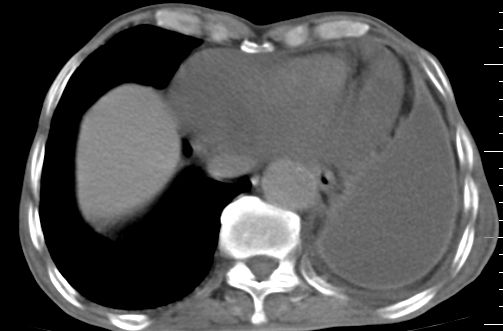

标题: CT10141:男、84岁,咳嗽、咯血1年。 [打印本页]

标题: CT10141:男、84岁,咳嗽、咯血1年。

支持左侧中央型肺癌伴下叶肺不张\\纵隔淋巴结转移.左侧包裹性胸腔积液\\心包积液.左侧少量胸腔积液..慢性支气管炎伴部分间质纤维化.

支持:左侧中央型肺癌伴下叶肺不张\\纵隔淋巴结转移.左侧包裹性胸腔积液\\心包积液.左侧少量胸腔积液..慢性支气管炎伴部分间质纤维化.另:支气管分支根部明显阻塞 狭窄,内膜凸凹不平,提示内膜增生物。

咯血病史较长,左肺下叶实变,体积未明显缩小,隐约可见血管影及坏死阴影,双肺门及纵隔淋巴结增大,心包增厚积液,纵隔右移位,单侧胸腔积液,首先考虑:大叶型肺泡癌伴纵隔心包转移。